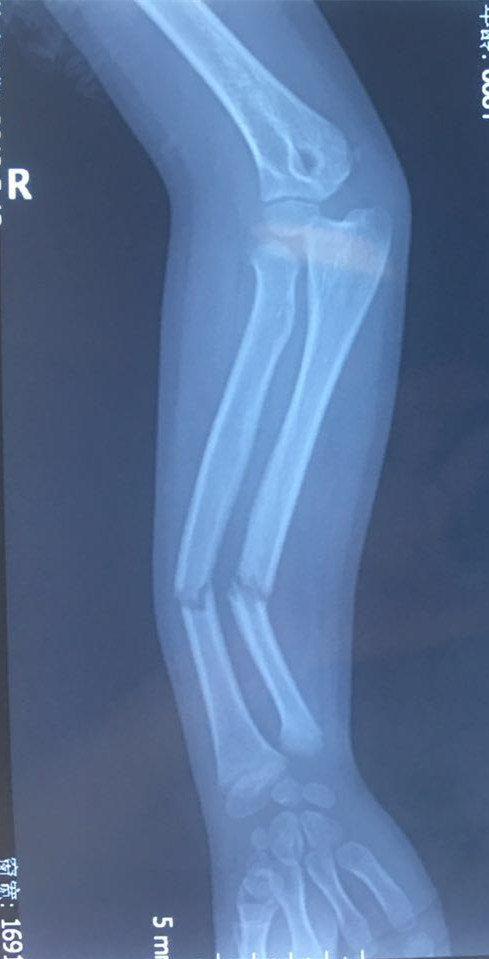

术前x光片,胫腓骨双骨折,成角移位

尺桡骨中段骨折 向桡侧掌侧成角明显

骨折的移位分析 成角移位